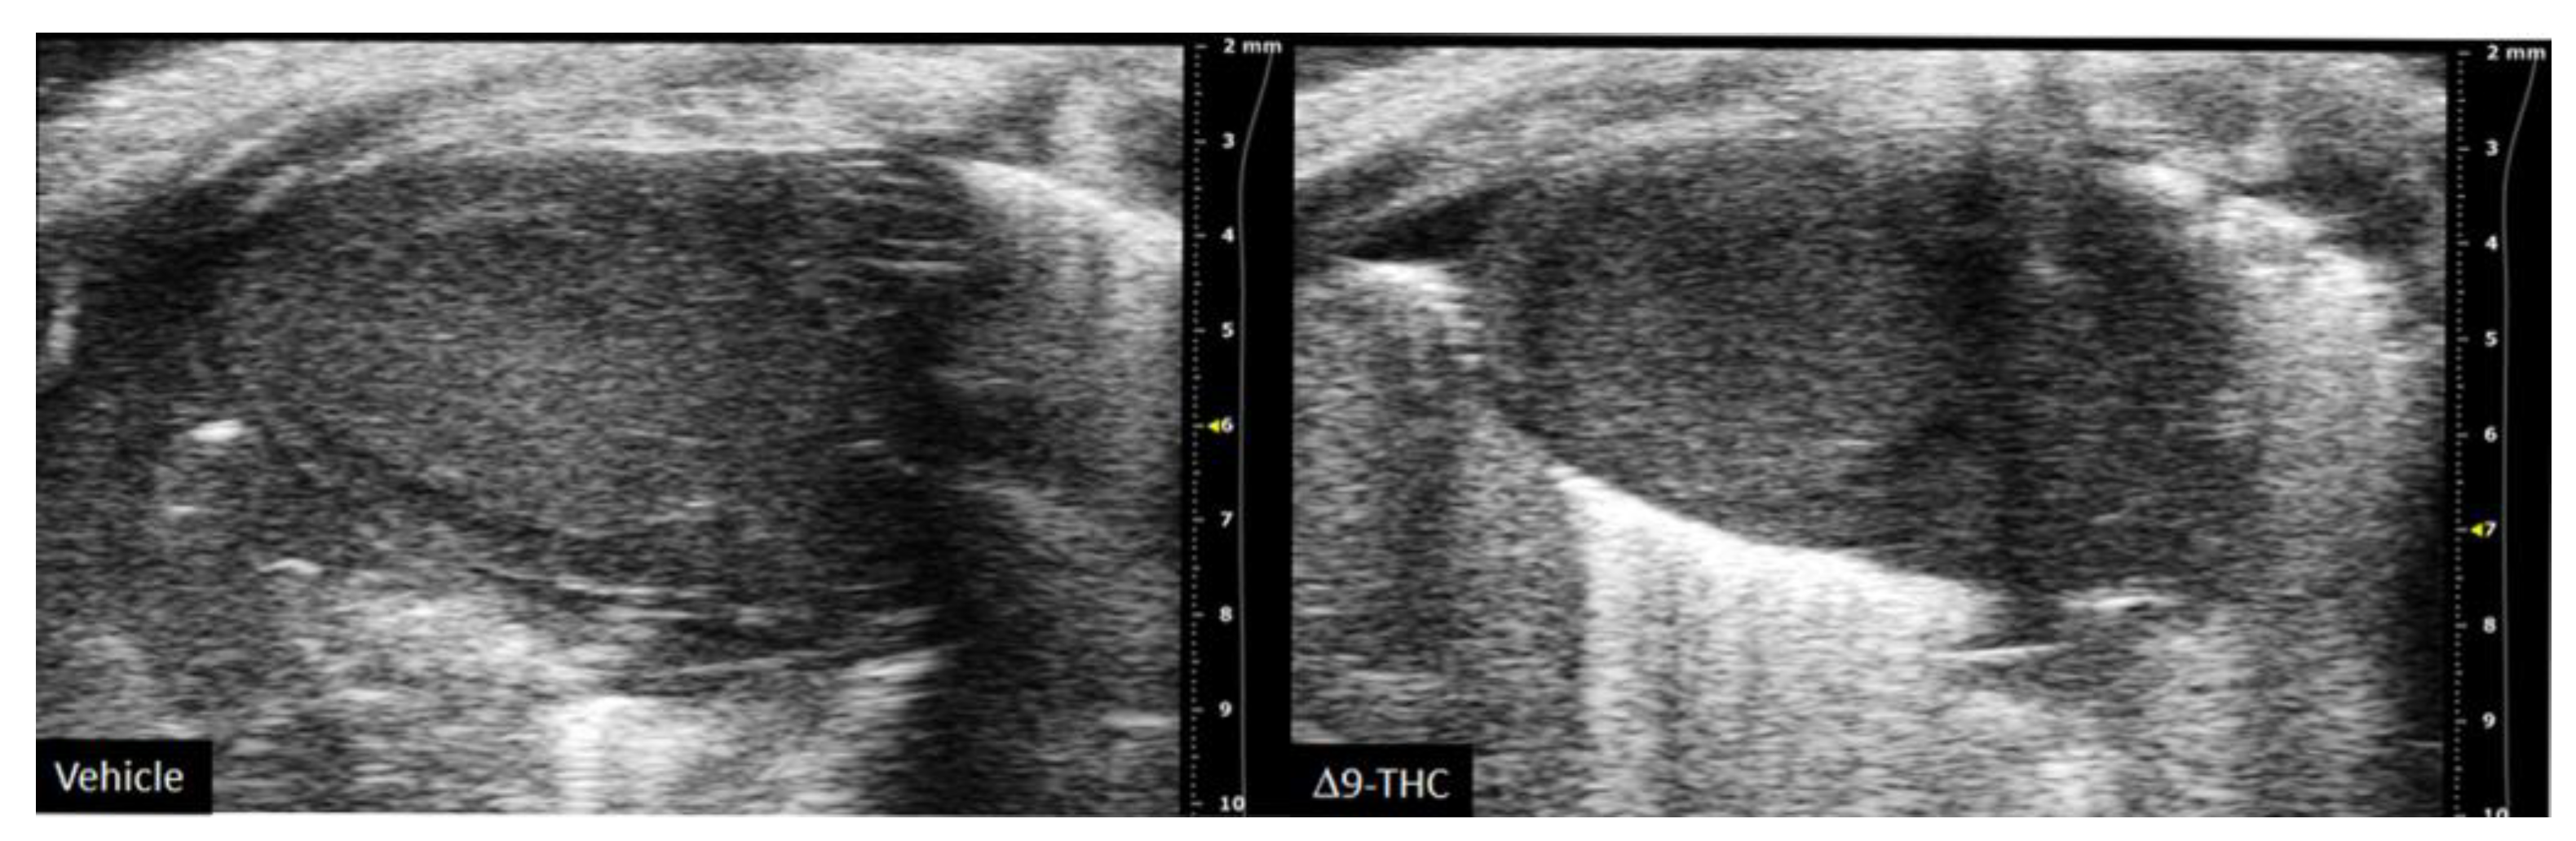

- Natale, B.V.; Gustin, K.N.; Lee, K.; Holloway, A.C.; Laviolette, S.R.; Natale, D.R.C.; Hardy, D.B. Δ9-Tetrahydrocannabinol Exposure during Rat Pregnancy Leads to Symmetrical Fetal Growth Restriction and Labyrinth-Specific Vascular Defects in the Placenta. Sci. Rep. 2020, 10, 544. [Google Scholar] [CrossRef]